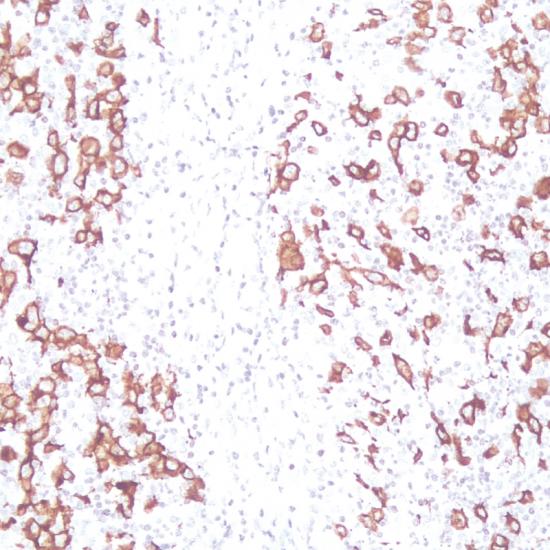

CD30

CD30抗體試劑(免疫組織化學(xué)) 閩廈械備20180068號

• 陽性部位:

細(xì)胞漿/細(xì)胞膜

• 陽性對照:

霍奇金淋巴瘤

CD30是腫瘤壞死因子受體超家族的成員,具有胞質(zhì)外結(jié)構(gòu)域、跨膜區(qū)域和胞質(zhì)結(jié)構(gòu)域。CD30表達(dá)于活化的T/B細(xì)胞、R-S細(xì)胞、部分淋巴濾泡周圍的轉(zhuǎn)化細(xì)胞、大多數(shù)間變性大細(xì)胞淋巴瘤細(xì)胞,在胚胎性癌中也發(fā)現(xiàn)CD30表達(dá)。此抗體主要用于標(biāo)記R-S細(xì)胞和大多數(shù)間變性大細(xì)胞淋巴瘤。